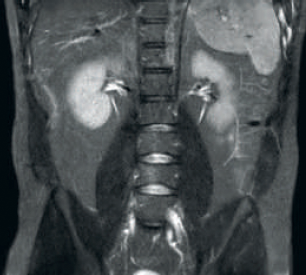

結果: SNRおよび画像解像度の改善

dStream RF受信技術により、MR信号をRFコイル内で直接デジタル変換できます。これにより、画像ボリューム全体にわたってSNRが最大40%向上¹しました。

Hennepin County Medical Center(HCMC)では、dStream技術を搭載するMR装置Ingenia 1.5Tを運用しています。*

* 非デジタル/dStreamシステムのAchievaと比較して信号対雑音比が最大40%向上しました。